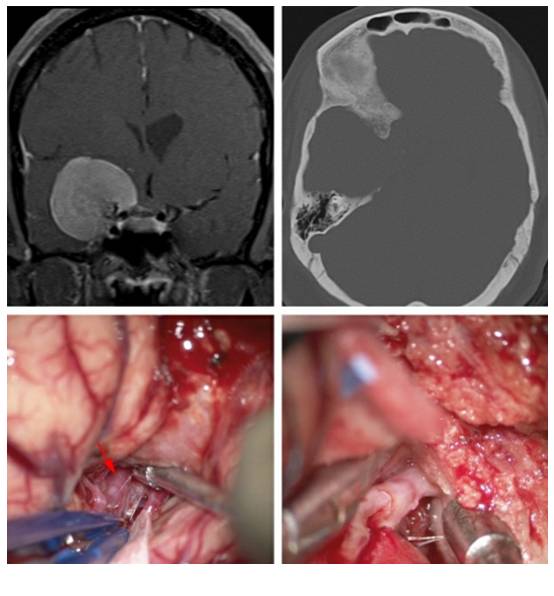

图7. 左侧扩大翼点开颅,切除床突后暴露肿瘤组织。在该病例中,大肿瘤由侧裂向外侧延伸。通过腰大池缓慢释放约40ml脑脊液后(每次释放10ml),可将肿瘤从蝶骨翼硬脑膜外侧游离出来,并电凝其内侧的硬脑膜附着点。该操作是手术中非常关键的一步,通过彻底阻断肿瘤血供,从而避免频繁的止血操作,加快后续的肿瘤切除过程。

图8. 笔者会沿着前颅窝继续阻断肿瘤血供,同时需注意视神经的大致位置,以避免热损伤的发生。脑脊液引流,侧裂分离和吸引器的合理使用,可避免使用固定脑牵开器。

图9. 对实性肿瘤,用超声吸引器(左图)进行去核和分块减压,而对较软的肿瘤组织,用双极电凝、吸引器和垂体咬钳进行减压。接着,笔者会轻轻地牵拉肿瘤包膜,使得其塌陷入已切除的肿瘤核心处(右图)。保持在肿瘤包膜内操作是非常重要的,否则会使得粘附在肿瘤内侧脆弱的脑血管结构受损风险增加。超声吸引器使用时需远离关键血管结构,否则即便没有直接接触,仍可能导致无法修复的血管损伤。

图10. 此时,在部分肿瘤减压,获得更多的操作空间后,笔者会进一步打开侧裂远端,辨别粘连在肿瘤上极和后极的M2分支血管。笔者还会沿着蝶骨翼,轻柔地向后方牵动肿瘤,以便发现或估计ICA在颅底的位置。这两步可以帮助笔者估计MCA分支,包括M1段,沿着肿瘤内侧包膜的走形,而此处正是笔者的盲点。

图16. 视神经充分减压,但是对于包裹血管的坚硬/钙化肿瘤组织,未予强行切除,以避免穿支动脉的损伤(上图)。下图术中图片所示,为肿瘤包裹了脉络膜前动脉或一根穿支动脉(箭头)。该小部分肿瘤未予处理。